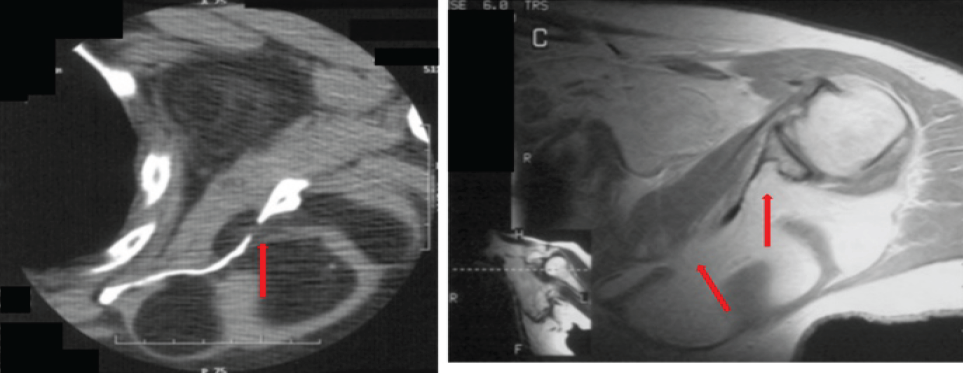

A 68 year-old man presented with a recurrent, non-painful mass in the right buttock. He had two prior resections at outside facilities. The first resection was of an intrapelvic mass performed 27 years before presentation through an anterior approach. The patient reported that this mass was a lipoma but no documentation of the histopathologic evaluation was available for review. The second resection was of a right buttock mass done 1 year before presentation through a posterior approach. Histopathologic interpretation of this mass at the outside hospital was that of a lipoma. Since the second resection, he noted a slow return of the mass along with pain in his right buttock that was associated with prolonged periods of sitting. On physical examination, there was a fullness of the right buttock with an apparent soft tissue mass that was soft and non-mobile. MRI demonstrated a mass that was hyperintense on T1 and T2 pulse sequences consistent with a lipomatous mass. The mass was predominantly in the buttock but extended through the sciatic notch into the retroperitoneal space (Fig. 2a). The majority of the mass appeared to be benign fat with some smaller areas with increased stranding. The mass abutted the posterior aspect of the ilium and appeared to have eroded through the posterior cortex in several places (Fig. 2b and c). There were no changes in the marrow adjacent to the erosions into the ilium. The changes in the ilium were better demonstrated on the CT scan with scalloping of the posterior ilium adjacent to the mass (Fig. 3a and b).

Figure 2: Case 2 magnetic resonance imaging T1-weighted imaging findings – axial (a) demonstrates a large fatty mass with some internal septations that extend through the sciatic notch into the retroperitoneal space (red arrow). (b and c) Demonstrates a large fatty mass that abuts the posterior aspect of the ilium which has eroded the posterior cortex in several places (red arrow).

Figure 3: Case 2 computed tomography imaging findings – axial. (a and b) Demonstrates scalloping of the posterior cortex of the ilium by a large low attenuation mass (red arrow).